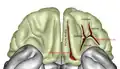

Orbital surface of left frontal lobe.

The inferior or orbital surface of the frontal lobe is concave, and rests on the orbital plate of the frontal bone. It is divided into four orbital gyri by a well-marked H-shaped sulcus the orbital sulcus.